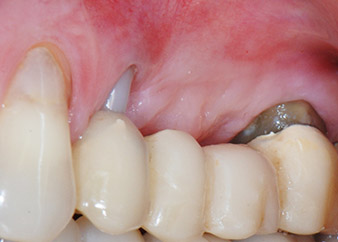

Zwischenergebnis nach zwei Monaten

Die Abbildungen 17 und 18 zeigen das klinische Ergebnis zwei Monate nach dem Eingriff. Die nun verminderte Beweglichkeit des Zahns 24 lag bei Miller-Klasse 1 und das Weichgewebe war entzündungsfrei. Um eine neue Infektion zu verhindern und das epitheliale Attachment nicht zu zerstören, wurde auf eine Sondierung zu diesem Zeitpunkt verzichtet. Die nächste Untersuchung sollte bei der Freilegung und dem Verschrauben der Gingivaformer stattfinden, sechs Monate nach dem Einsetzen der Implantate.

Zwei Monate nach dem Eingriff ist die Patientin schmerzfrei.

Abb. 17: Zwei Monate nach dem Eingriff ist die Patientin schmerzfrei und der Bereich weist keine Entzündungen auf.

Nach dem Eingriff

Abb. 18: Zahn 24 zeigt eine verminderte Beweglichkeit.